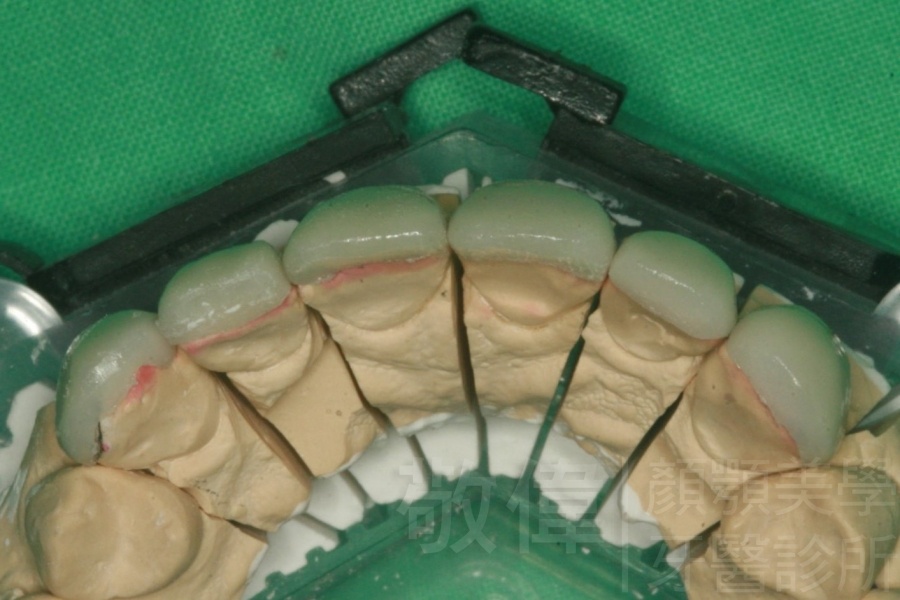

| 8 | 前牙美容 | 快速矯正之美容晶瓷貼片及晶鑽瓷冠 | ||

| 9 | 前牙美容 | 矯正+美容晶瓷貼片 | ||